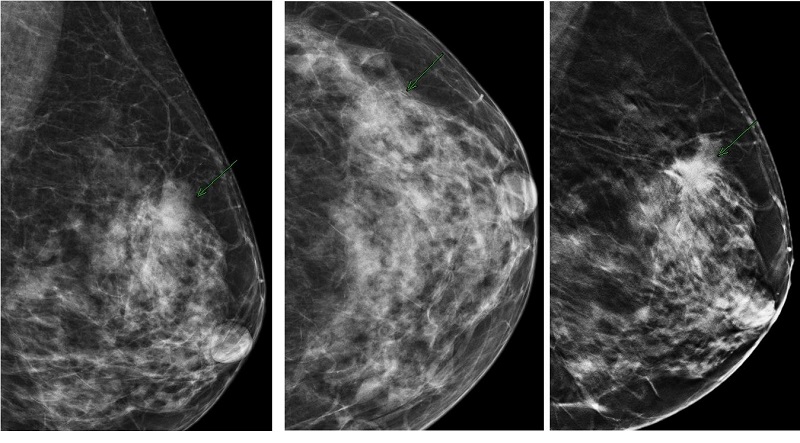

Chụp X quang tuyến vú (mammography hay chụp nhũ ảnh) là một phương pháp chẩn đoán hình ảnh sẽ sử dụng tia X để tạo ra hình ảnh chi tiết của tuyến vú. Đây là kỹ thuật quan trọng trong việc phát hiện sớm ung thư vú và các bệnh lý khác liên quan đến tuyến vú.

Hình ảnh trả về từ chụp X quang vú